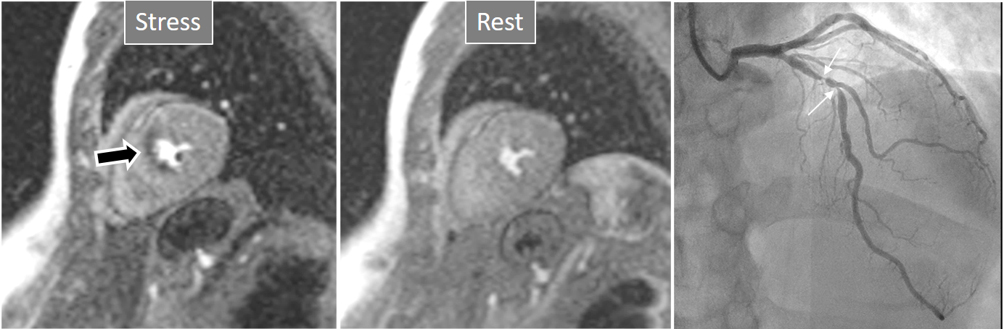

The aim of perfusion studies is the demonstration of a blunted increase—or a reduction—in regional MBF in response to a vasodilator stimulus which can be attributed to a flow-limiting coronary artery lesion. Rest perfusion studies alone are not useful in this sense, as basal MBF is kept within normal limits even in territories supplied by a severely stenosed vessel, and is only after a vasodilator agent has been given that the reduction in CFR can be evidenced [24]. In CMR studies, this situation is detected as a reduced increase in SI of the underperfused territories (Fig. 3).

Fig. 3.Induced perfusion defect. Subendocardial perfusion defect at the interventricular septum during stress (left panel, black arrow), not present at rest (middle panel), in a patient with significant coronary stenoses in the left anterior descending (LAD) artery (right panel, white arrows).

The most immediate and commonest method of analysis is the visual detection of a distinctive deficient increase in signal intensity of a region of the left ventricular myocardium during the first passage of a CA bolus under vasodilatory conditions lasting for at least 3 consecutive frames of the sequence. This perfusion defect should not be present at rest and should not correspond to an area of previous MI. The detection of such a defect is assumed to be due to a reduction in CFR of this territory which, when attributed to a particular coronary artery [39], allows for the conclusion of the presence of a significant epicardial stenosis in the vessel (Fig. 6).

Fig. 6.Single-vessel perfusion defect. Extensive subendocardial perfusion defect at the antero-septal region (arrow, on the upper left panel) not present at rest, in a region without LGE (lower left panel). Angiography proves this defect to be due to a tight stenosis of the LAD coronary artery (arrow, on the lower right panel).